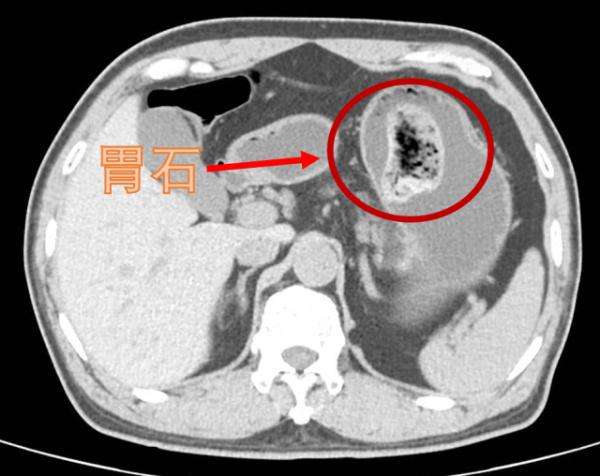

日前,50岁的伍先生因腹部长期反复胀痛到医院就诊,经胃镜检查后发现胃里竟长了块拳头般大小的“石头”,且胃壁遍布大大小小的溃疡。

接诊并仔细询问伍先生的病情后,练磊判断,正是因为这块直径有10厘米的“拦路石”把胃通向肠子的通道堵塞住了,导致食物长期淤积在胃里,让伍先生感觉反复腹胀。而他的胃溃疡也是因此而起。

△伍先生胃里的胃石

经过详细检查,医生发现这块石头太大了,无法从食道直接取出。如果放任不管,胃石会一直磨损胃黏膜,加重溃疡,甚至会引发癌变。因此,医生用“微创胃取石术”的方案成功并完整地取出胃石。